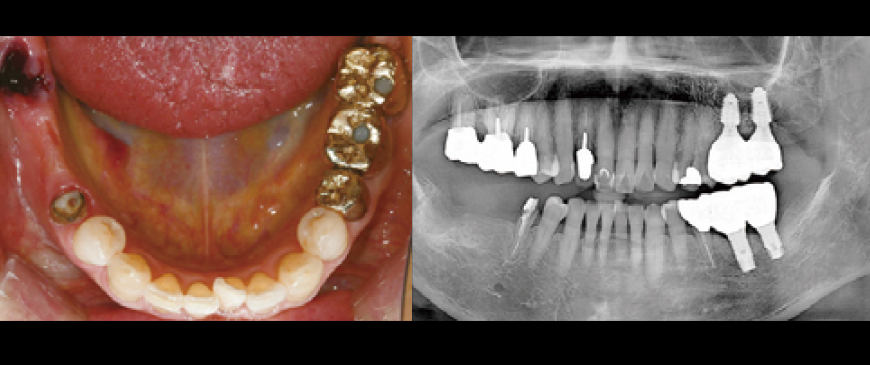

An elderly female patient in her mid-80s required implant treatment due to the loss of abutment teeth supporting the bridge in the right mandibular posterior region.

Fig 2

Intraoral and CBCT radiographic images revealed that the pontic area of the long-edentulous bridge site had developed a significantly thin ridge over time.

Fig 3

Upon flap elevation, it was confirmed that the first molar region also exhibited a significantly thin ridge condition.